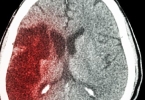

脑出血量是核心预后指标。30毫升以下出血经及时清除血肿后,患者五年生存率可达60%以上;超过50毫升的大出血即使手术成功,常遗留严重神经功能障碍。出血量直接影响脑组织受压程度,术后需通过CT动态监测再出血风险。

黄金抢救期为出血后4-6小时,此时手术能最大限度挽救濒死脑细胞。超过24小时才接受开颅的患者,脑水肿和继发损伤已形成,术后生存期可能缩短30%-50%。急诊CT评估后需立即决定手术方案。